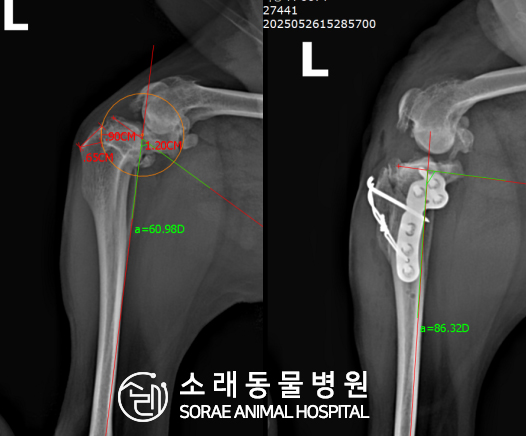

계산식으로 사전에 계획해두었던 플랜에 따라 경골을 절제하고

플레이트와 스크류를 사용하여 임플란트를 적용해 주었습니다.

반대 방향으로 밀려나 어긋나있던 대퇴골과 정강이가

제 자리를 찾으면서 무릎의 각도가 교정된 것을 확인할 수 있습니다